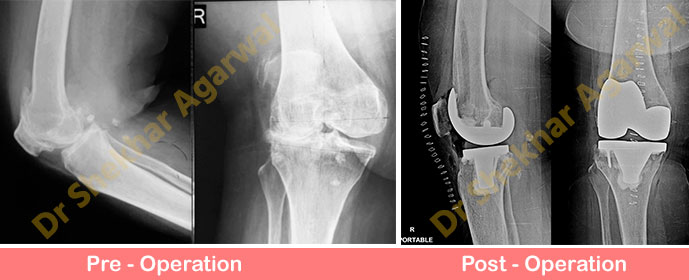

60 years old lady had difficulty in walking. She had osteoarthritis of right knee with valgus deformity.

On examination the knee had fixed valgus and flexion deformity and painful range of motion.

These cases require meticulous planning and soft tissue releases to balance the knee than the usual varus OA knee. There is also increased risk of maltracking of patella and peroneal nerve palsy.

We did Total Knee Replacement using posterior stabilized primary knee implant. We recommend that constrained knee implants should always be kept as backup when operating such cases. Post op xray showing well balanced and aligned knee with knee prosthesis. The patient is comfortable after surgery and walking independently.